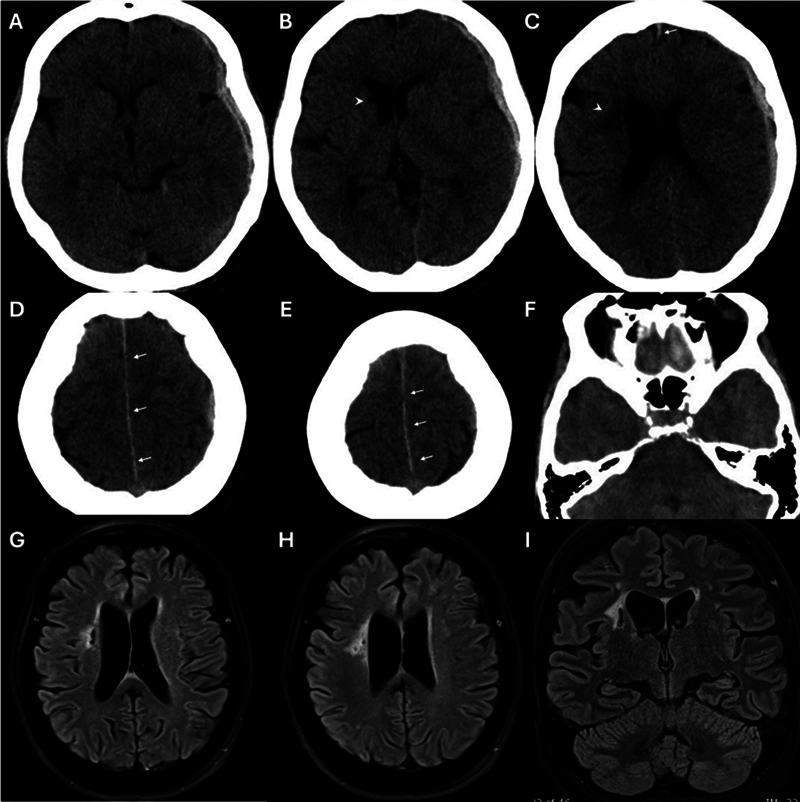

Spontaneous acute subdural hematoma is uncommon and usually caused by coagulopathy or other bleeding disorders, malignancy, intracranial hypotension, and abnormal intracranial vessels. We present unique cases of acute spontaneous subdural hematoma from moyamoya disease. There are a few cases reported, and we review previous literature and describe bleeding sources from aneurysms related to moyamoya disease in highly unusual locations.